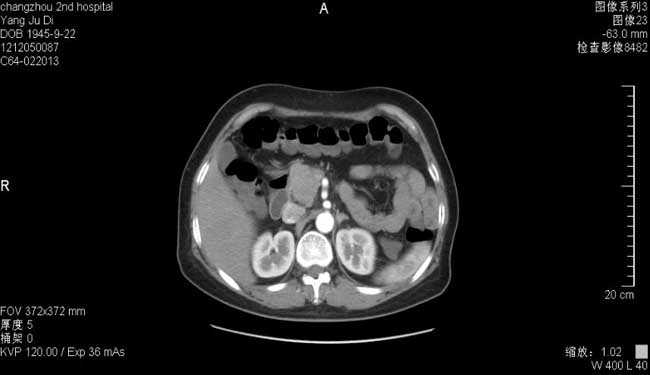

全腹部CT示:1.胰腺头颈部占位(4.0*3.5*3.5cm),MT可能,胰头后缘结节状软组织密度影,肿大淋巴结不除外。2.臀部多发肿块(最大5.6*3.6*5.5cm),转移可能大。3.胃底部胃壁可疑稍增厚,轻度食管裂孔疝?4.肝脏囊肿,左肾囊肿。5.胆囊小结石。